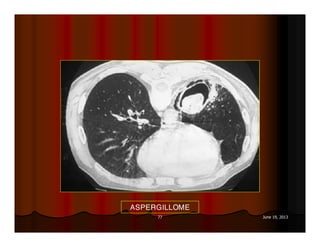

ASPERGILLOME

DẤU HIỆU LỤC LẠC

(SIGN OF TINTINNABULUM)

Sign of tintinnabulum = Signe de grelot.

Nấm Aspergillus có thể gây bệnh ở người với 2 thể chính:

Thể xâm lấn mạch máu (Angioinvasive Aspergillosis): tổn

thương lan toả, gặp ở người có cơ địa suy giảm miễn dịch. Ở

thể này ta có dấu hiệu vầng hào quang (halo sign) trên CT.

Thể banh nấm (Saprophytic Aspergillosis = Aspergilloma):

hình thành banh nấm (fungus ball) trong lòng các tổn thương

hang ở phổi, thường gặp ở BN có hang lao. Thể này cho dấu

hiệu lục lạc (Tintinnabulum sign) hay dấu hiệu liềm khí (Air

crescent sign) tuỳ theo tác giả.